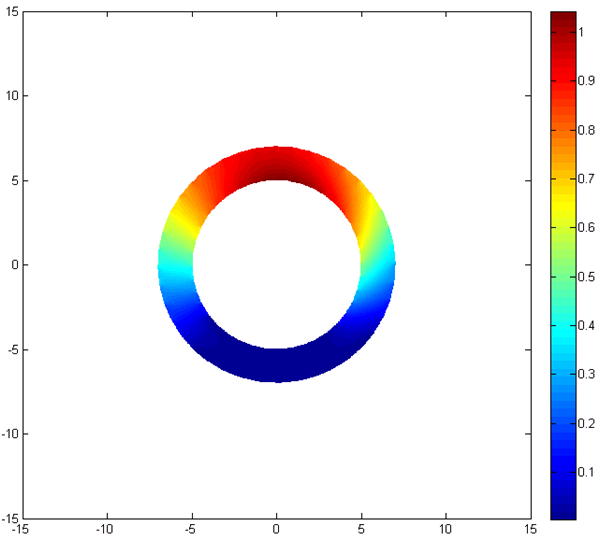

After the analysis with ANSYS, the proposed model should be implemented and the results should be compared and verified with the results of ANSYS analysis. At first the inner and our contours of the ring is determined. Then, after setting the boundary conditions, the governing equation of deformation is solved using FEM and the deformation maps are created. All the code is implemented in MATLAB.

Fig. 4 represent the results of the proposed method for both horizontal, vertical and absolute displacement. To better be able to compare the results, the ring is divided into 16 sub-regions and the results of ANSYS and MATLAB implementations are compared. Fig. 5 shows the average displacement in each region for 10 iterations of pressure increment for both ANSYS and proposed method. Based on the provided results, it can be seen that the proposed model is consistent with the results of ANSYS, even in regions with low mobility (regions 11, 12, 13 and 14).